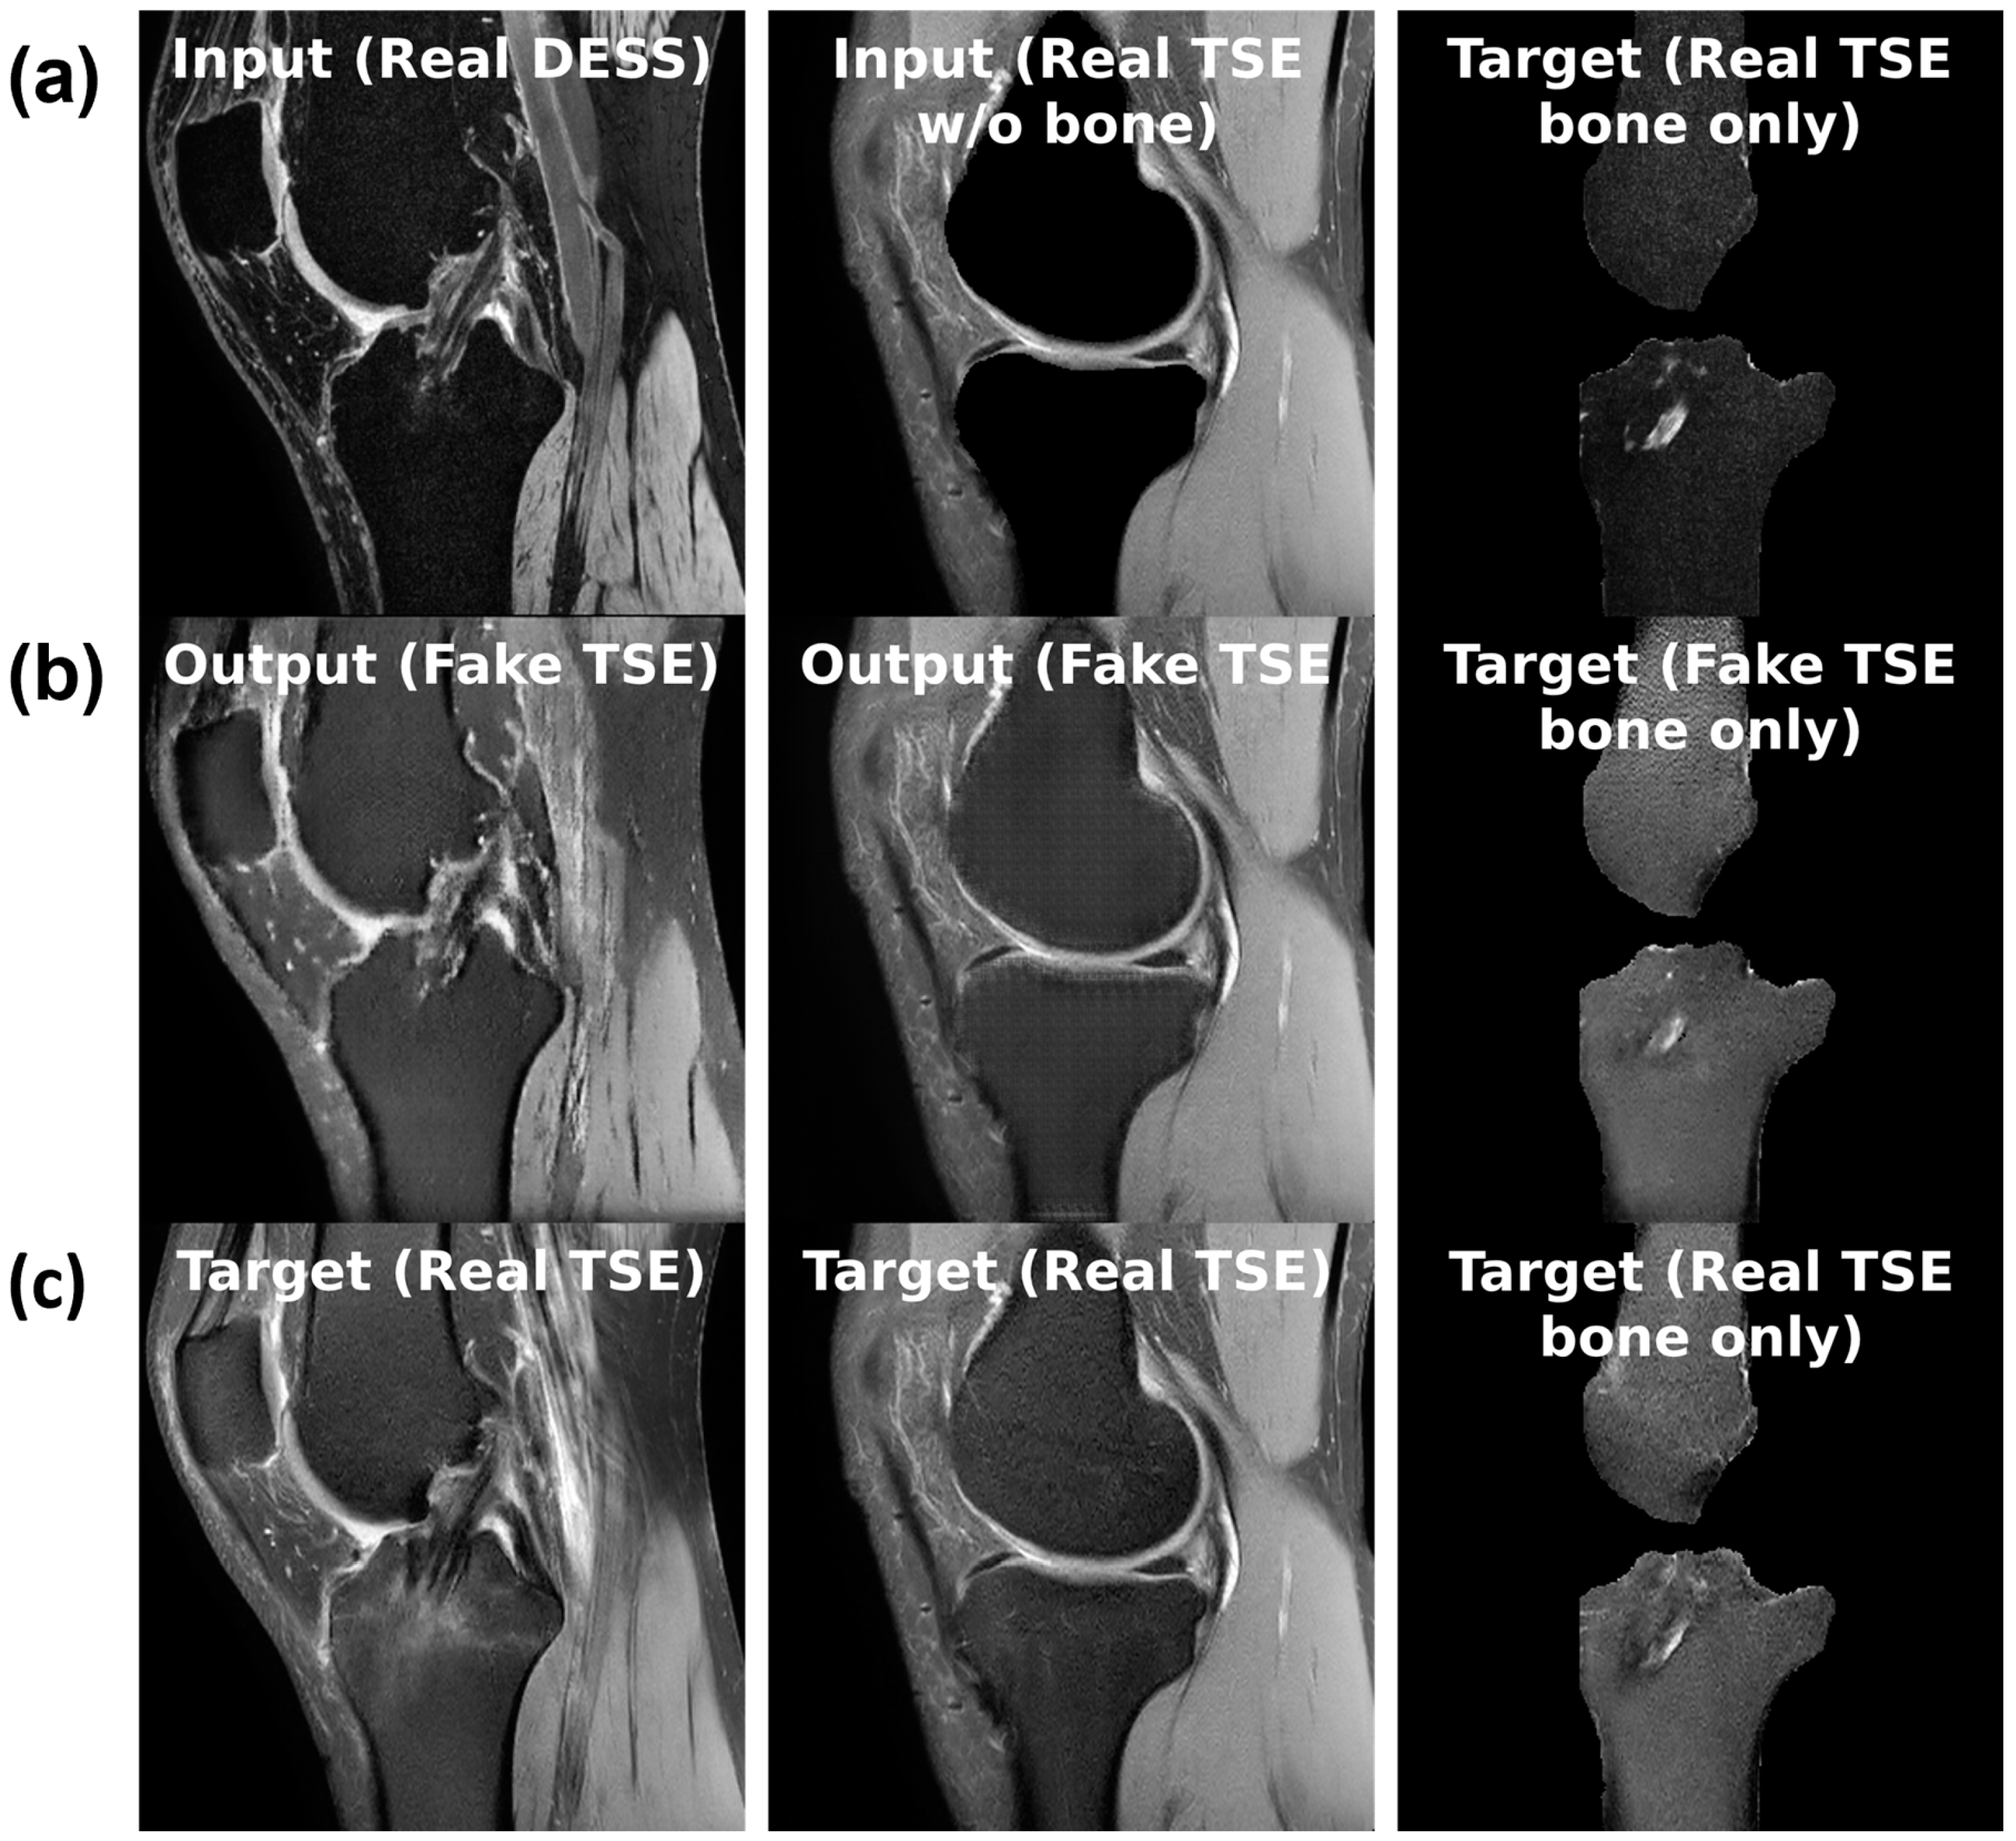

Figure 4. (a) Sample inputs (top row), (b) outputs (middle row), and (c) targets (bottom row) for each of the three tasks from left to right: slice translation; bone inpainting; and bone translation.

For the sequence translation task shown in Figure 4a, DESS is the input sequence and TSE is the output sequence. During training, the model gets a full view of the input DESS image and learns to synthesize the corresponding TSE image. Since these images are co-registered and most structures are consistent across the sequences, the model can learn this task. Furthermore, the training dataset only consists of healthy, BMEL-free images, which means the model will always synthesize a healthy TSE image given any DESS image, even if the real TSE image contains a BMEL. Therefore, DESS is the preferred input sequence since it has low signal intensity difference in healthy and BMEL regions; healthy and unhealthy DESS images look similar. Conversely, TSE is the preferred output sequence since it has high signal intensity difference in healthy and BMEL regions. The resulting anomaly map is computed by taking the difference between the real unhealthy TSE image and the fake healthy TSE image.

For the bone inpainting task shown in Figure 4b, both input and output sequences are TSE, except the input image has its bone regions removed using the bone segmentation masks. To reconstruct the full TSE image as output, the model learns to inpaint the bone given the surrounding regions, such as cartilage, muscle, etc. Again, the model is trained only on healthy images, which means it will inpaint a healthy bone region whether or not the real bone region contains BMEL or not. The bone mask is a suitable region to inpaint because by definition, BMEL occur inside the bone region and will always be inpainted.

Another task, called the bone translation task shown in Figure 4c, is also considered. In this case, only the bone regions of both DESS and TSE sequences are kept; non-bone regions are masked out using the bone segmentation mask. After this step, the task proceeds like sequence translation: DESS sequence is the input and TSE sequence is the output. This task may have the advantage of removing confounding factors in the surrounding regions around the bone that may not be relevant to the generation of the anomaly map.

The models performed similarly at their best, albeit on different tasks: bone inpainting and sequence translation for cGAN and cDIFF, respectively. Examples of the sequence translation task on cDIFF are shown in Figure 7. Another metric of note is the parameter count for each; cDIFF has nearly tenfold the number of parameters when compared to the cGAN. The best performing cDIFF model trained on the sequence translation task was configured as follows: batch size of 6; Adam optimizer with a fixed learning rate of 1 × 10 4 [32]; Kaiming model parameter initialization [33]; and a quadratic noise schedule with 1000 timesteps as described by Nichol et al. [34]. The best performaing cGAN model trained on the bone translation task was configured as follows: batch size of 36; Adam optimizer with a fixed learning rate of 5 × 10 4 ; model parameters initialized to zero; and PatchGAN discriminator with three convolutional layers. More details are given in Section 2.5.